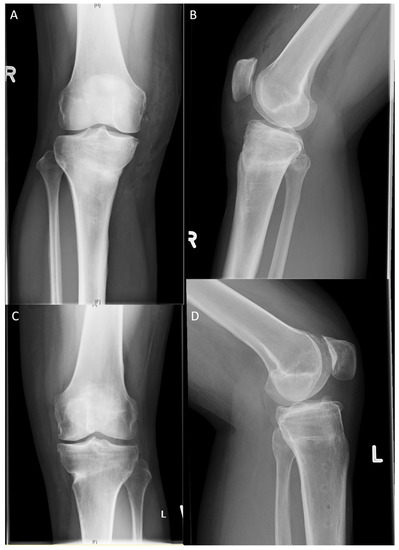

2.2. Surgical Technique

3.5. Radiological Signs of Implant Failure and Healing Rate on the 12-Month Radiographs